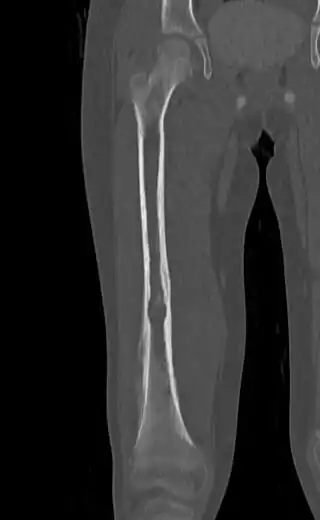

![]() ![]() | |

| Top: Ewing sarcoma of the thigh bone on a child's CT scan Bottom: Extraskeletal Ewing sarcoma of the hard palate | |